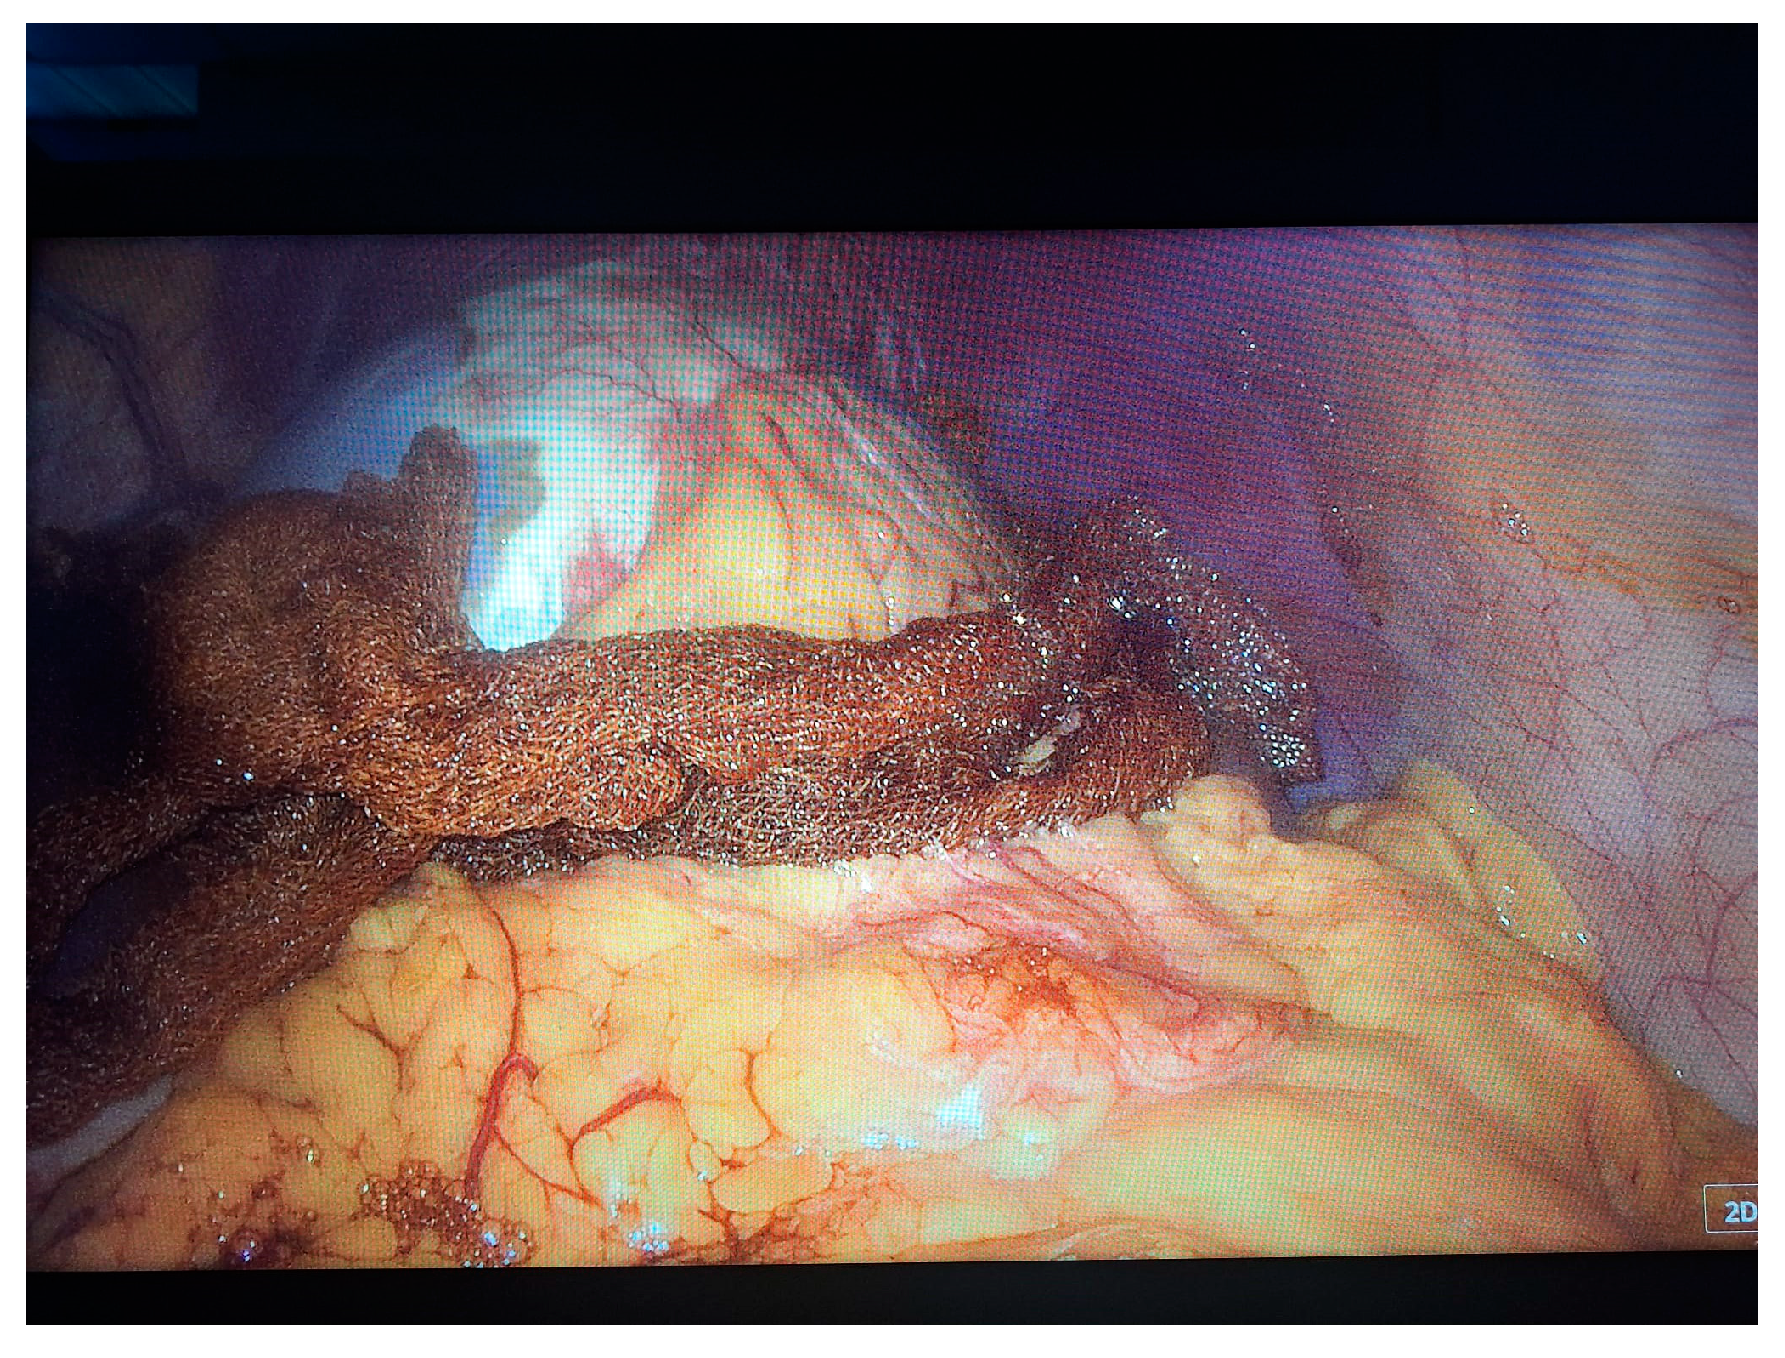

2. Case Presentation

- Grade I splenomegaly with simple voluminous splenic cyst, 10 cm in diameter.

- Accessory spleen adjacent to the lower pole of the spleen.